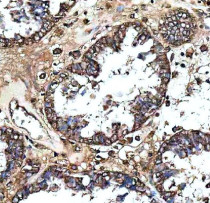

ARG45912 anti-MS4A4E antibody IHC-P image

Immunohistochemistry: Human ovarian cancer stained with ARG45912 anti-MS4A4E antibody at 2 μg/ml dilution.